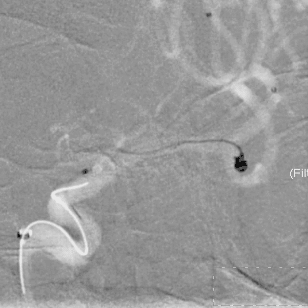

栓塞过程

栓塞微导管精准塑形后,前推顺利到位,依次填塞三枚Jasper®SS弹簧圈,瘤颈处有壶腹,为增加弹簧圈稳定性,降低动脉瘤复发率,释放一枚支架。

术后即刻影像